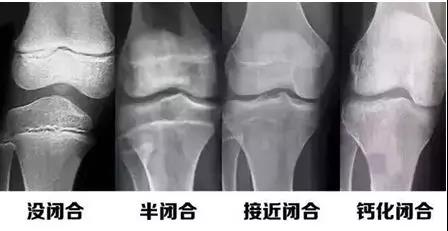

人的生長發(fā)育的程度可以用兩個(gè)年齡來表示,即生活年齡(日歷年齡)和生物年齡(骨齡)。

而骨齡和兒童身高之間有著密切的關(guān)系,通過骨齡可以及早了解兒童的生長發(fā)育潛能以及性成熟的趨勢,還可預(yù)測兒童的成年身高。